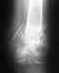

43,172,81.Травма 3 года назад.Перелом верт.впадины,перелом сед.костей,компр.перелом L1-th12.Сильные боли в левом суставе и вокруг него.Если возможно определить по снимкам нужно ли хирург.лечение?

Если есть болезненные проявления, то нужно. Похоже, нет перспективных вариантов, кроме замещения сустава.